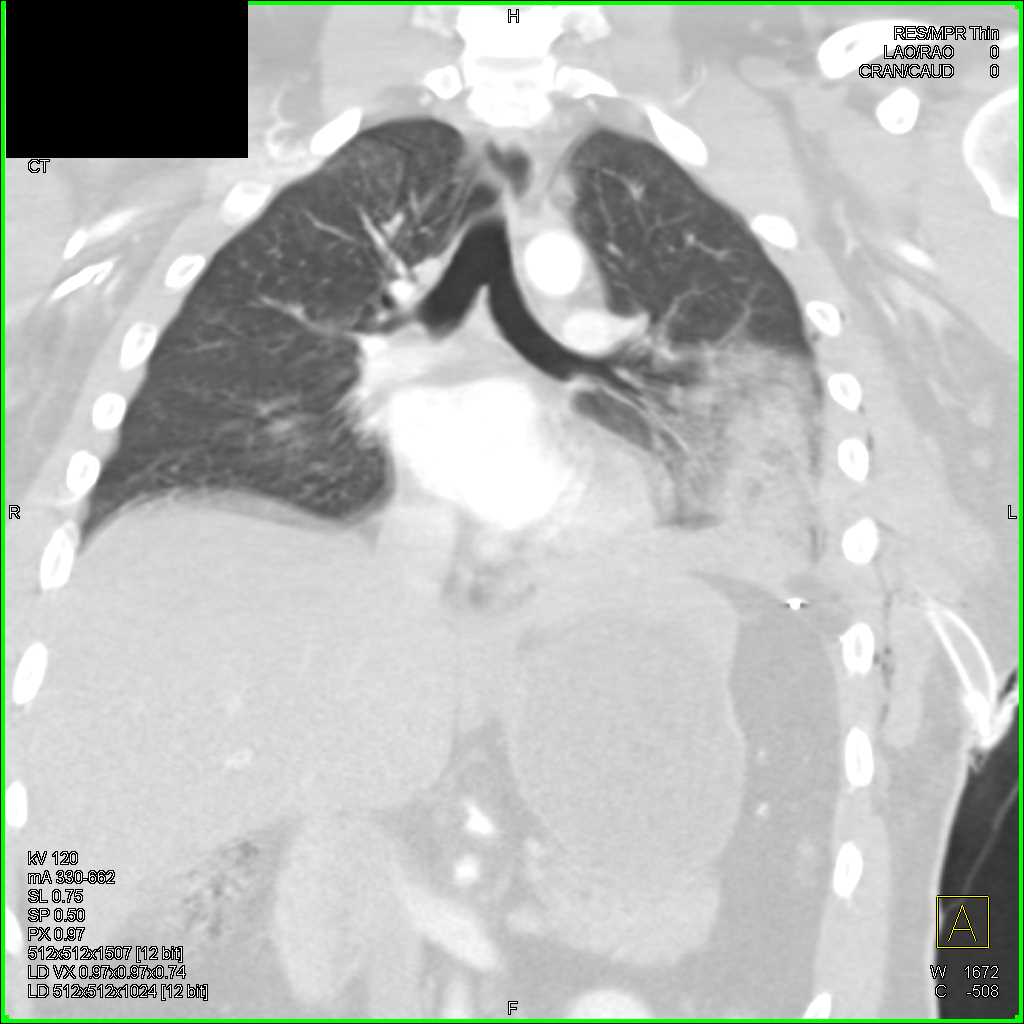

Trauma with Pulmonary Contusion and Rib Fractures Trauma Case Studies

from www.ctisus.com